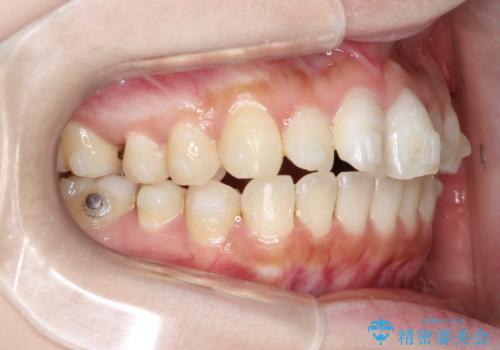

【インビザライン】矮小歯を有する方の治療②

- 前歯の凸凹を主訴に来院されました。

左上の前歯が元々小さいため、前歯の真ん中が揃わないことを伝えた上で矯正治療を開始しています。

スペースを作るために遠心移動ろIPRをおこなて治療を行いました。